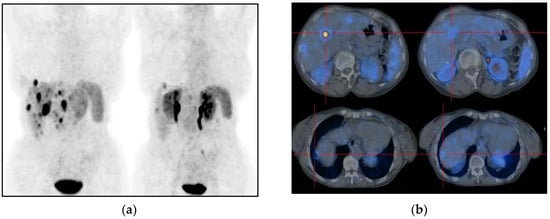

- Venema, C.M.; Mammatas, L.H.; Schroder, C.P.; van Kruchten, M.; Apollonio, G.; Glaudemans, A.W.J.M.; Bongaerts, A.H.H.; Hoekstra, O.S.; Verheul, H.M.W.; Boven, E.; et al. Androgen and estrogen receptor imaging in metastatic breast cancer patients as a surrogate for tissue biopsies. J. Nucl. Med. 2017, 58, 1906–1912. [Google Scholar] [CrossRef]